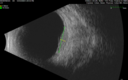

51 year old female with metastatic breast cancer to her bone and brain. She was told about a month ago that there were tumors in her eye. Her vision in the right eye has been declining for a few weeks. VA 20/63 OD, 20/32 OS Her choroidal lesions did not shrink with systemic therapy so in April 2021, she had external beam radiation x 15 sessions and the tumors shrank (4th and 5th set of images)

Bilateral Choroidal Tumors - Metastatic Breast Cancer286 views51 year old female. First 3 sets of images show lesions growing despite systemic chemotherapy. She eventually had external beam radiation x 15 sessions and the tumors shrunk in the last two sets of images00000